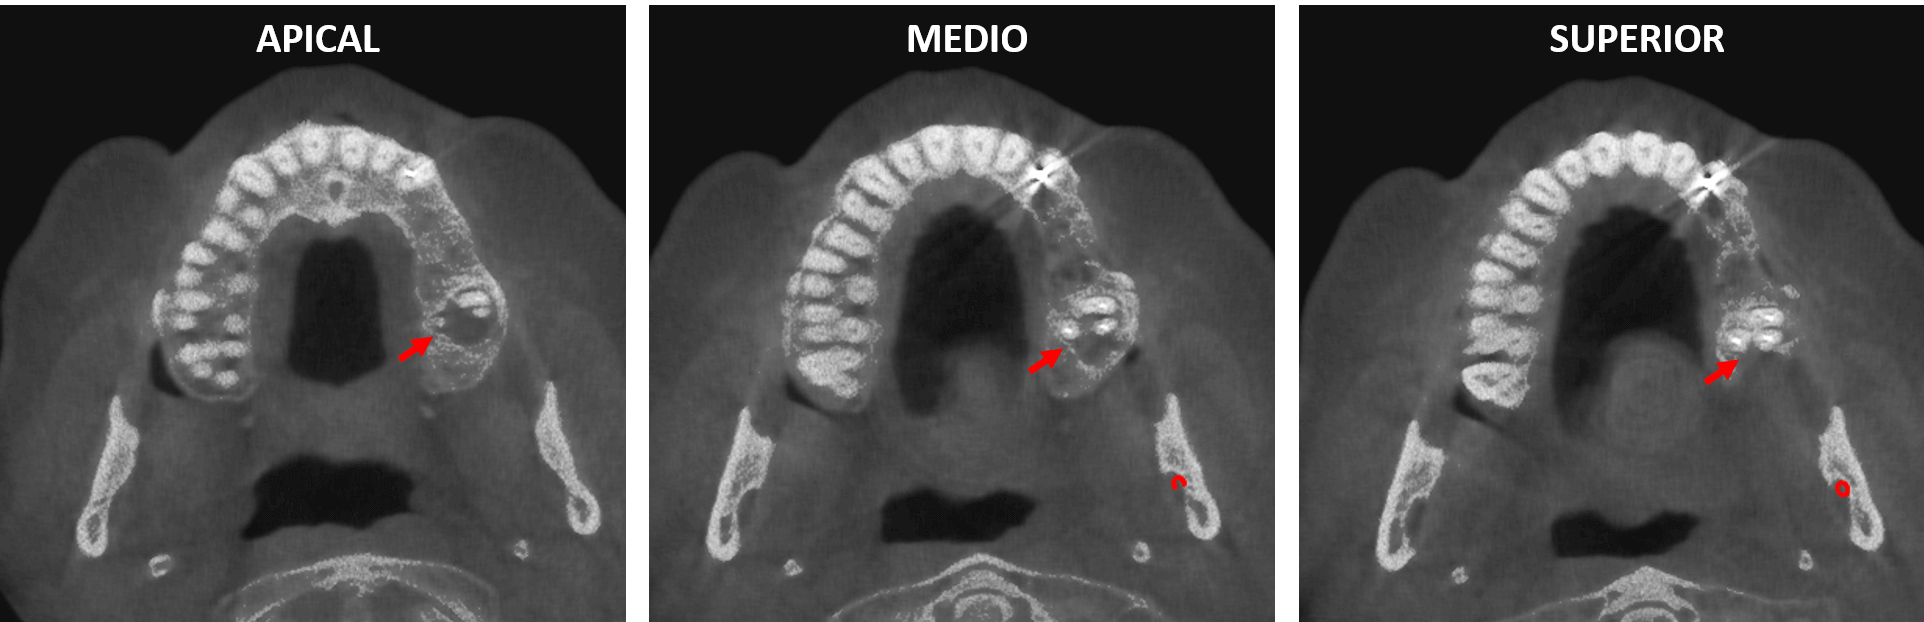

Fig.3

En la reconstrucción panorámica del maxilar superior y cortes transaxiales del órgano dentario 27 (Fig.3), donde se observa la lesion osteolítica en el hueso alveolar que se extiende hacia el seno maxilar y el aumento de la densidad ósea circundante compatible con osteítis condensante. Nótese en la reconstrucción panorámica del maxilar superior una lesión osteolítica a nivel apical en el órgano dentario 23.